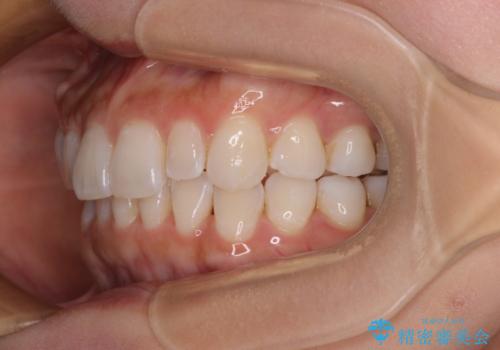

【モニター】前歯のデコボコと小さい前歯 インビザライン矯正とオールセラミッククラウン補綴治療

- 前歯の歯並びと生えてきたときから小さい前歯を気にして来院された患者様です。

上下前歯の歯列不正はインビザラインにより整え、その後に、矮小歯の前歯をオーダーメイドタイプのオールセラミッククラウンにて補綴治療することとしました。

セラミッククラウンにて大きさを変更することを前提に矯正治療を開始したため、大変満足のいく仕上がりとなりました。